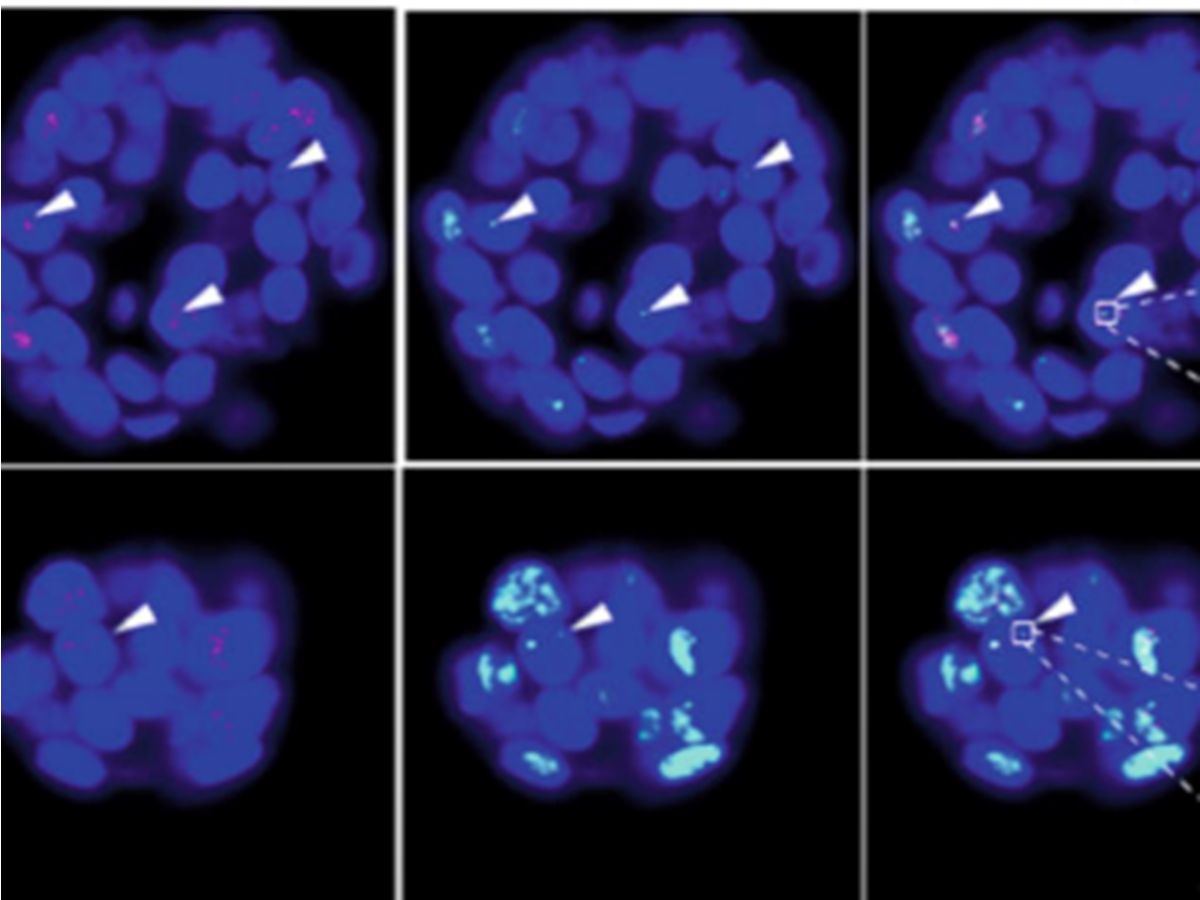

p-care partner Stefan Schoeftner and his team at the University of Trieste publish a scientific article involving the use of tumor-organoids to provide insights into mechanisms of cancer cell immortalization (Nature Communications)